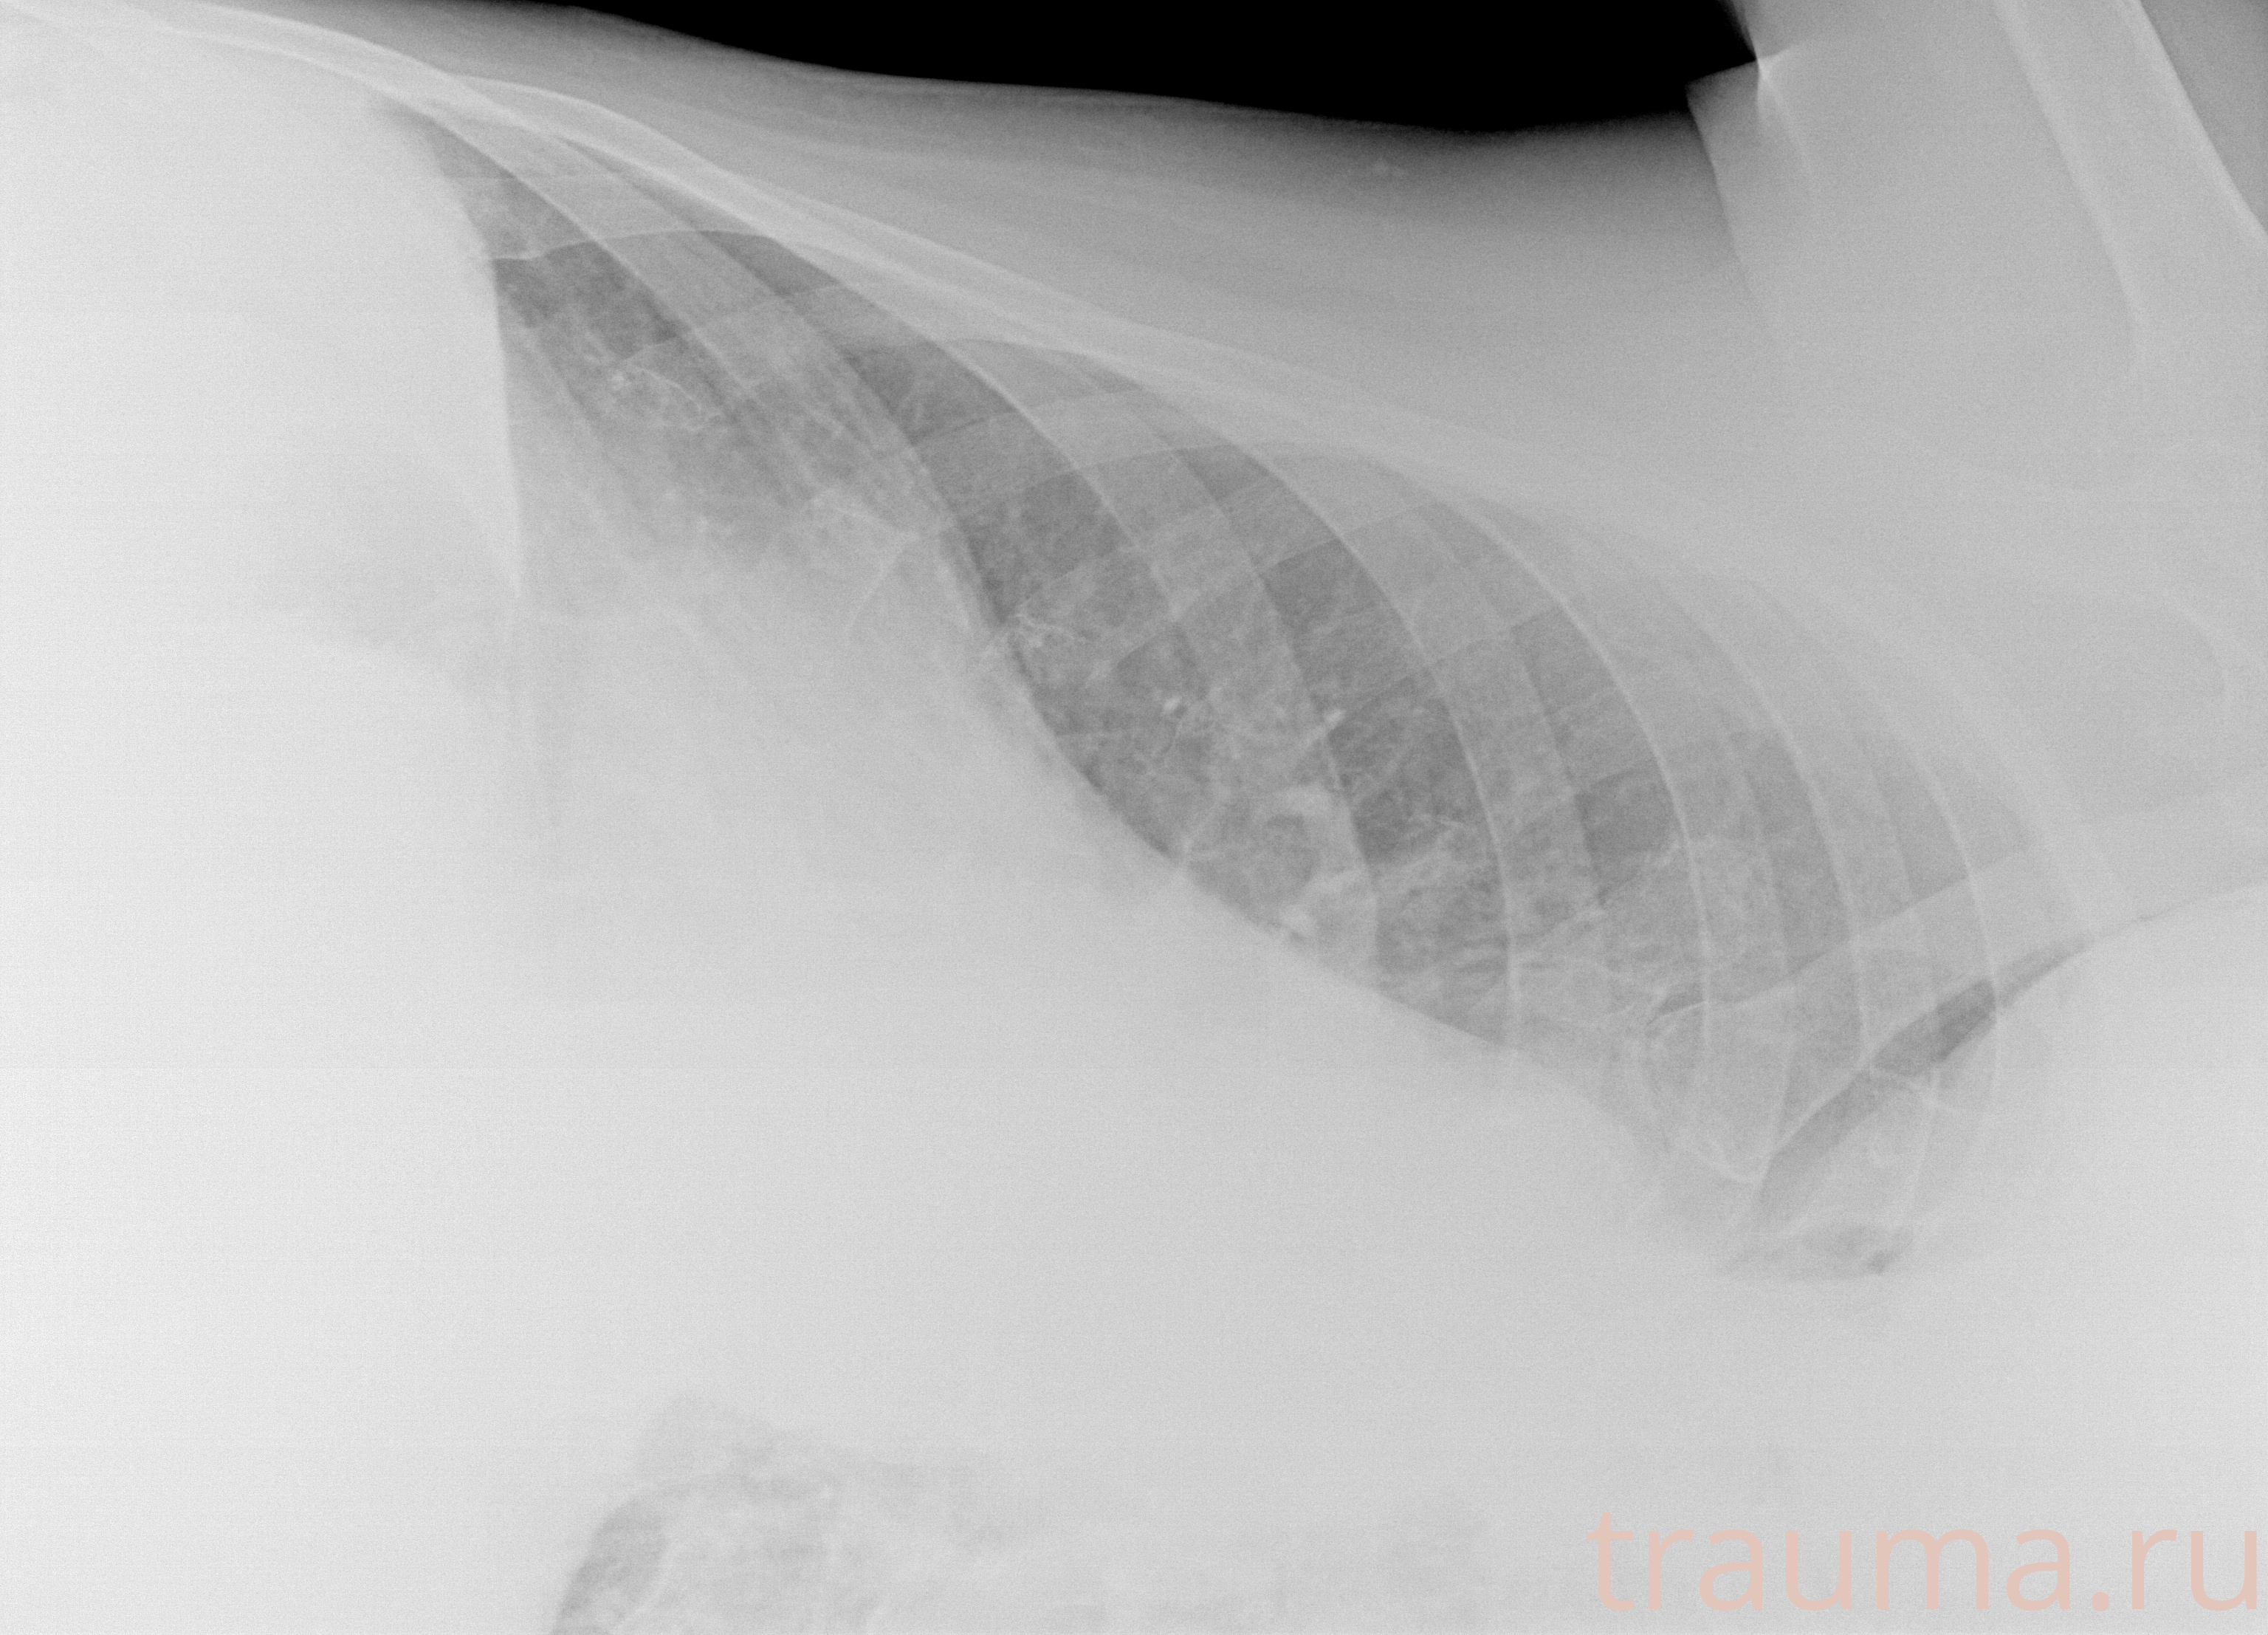

Рентгенограммы

Рентген на дому: по вашему адресу приезжает врач-рентгенолог, травматолог-ортопед с мобильным рентгеновским аппаратом, проводит диагностику травмы или заболевания, делает необходимые рентгенограммы, дает рекомендации по дальнейшему лечению. Получить качественные снимки в домашних условиях возможно благодаря уникальной методике, разработанной МосРентген Центром для института  Склифосовского

Яркость: 1   Контраст: 1   Инвертировать: 0 Увеличение: 1

Перетаскивайте мышь вверх/вниз для контраста, влево/право для яркости. Прокрутка колесом изменяет масштаб. Нажмите Сбросить для возврата к исходному изображению. При увеличении держите мышь в той области, которую хотите рассмотреть.